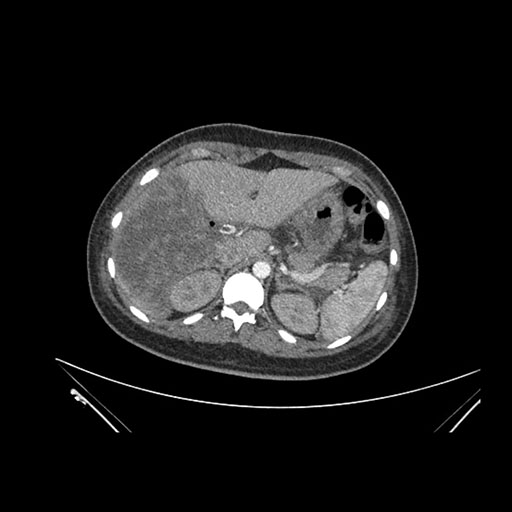

Imaging Analysis

Look through the patient's CT scan to identify any areas of concern for the necessary procedure.

Axial Arterial

Axial Venous